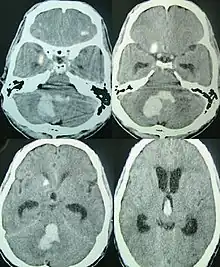

![]() | |

| CT scan of a spontaneous intracerebral bleed, leaking into the lateral ventricles | |